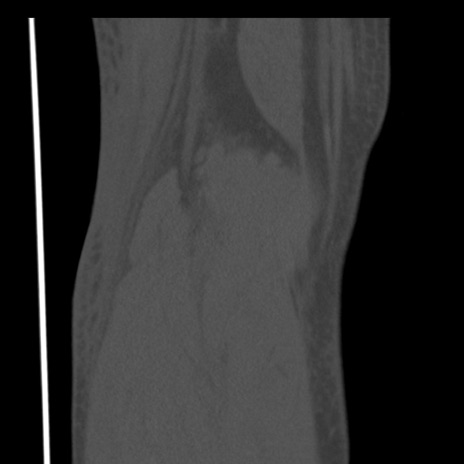

右膝関節CT

矢状断像